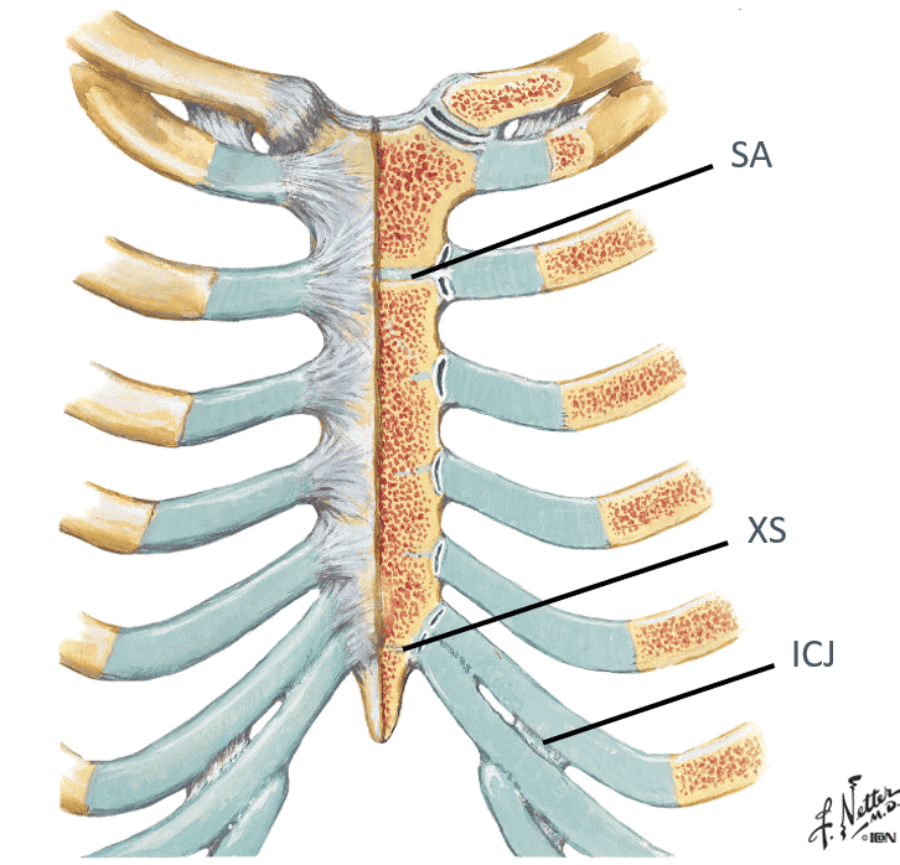

Identify/describe the joints of the anterior thorax and what they articulate with?

- Interchondral joints (ICJ)

- “articulation” between costal cartilages of lower ribs

- Manubriosternal joint (sternal angle – SA)

- Xiphisternal joint (XS)

- junction of xiphoid and sternum

Interchondral joints (ICJ)...“articulation” between costal cartilages of lower ribs

Manubriosternal joint (sternal angle – SA...manubrium and sternal body meet)

Xiphisternal joint (XS)...junction of xiphoid and sternum

essentially, the interchondral joints is where what articulates with what?

where the false ribs articulate with the cartilage above it